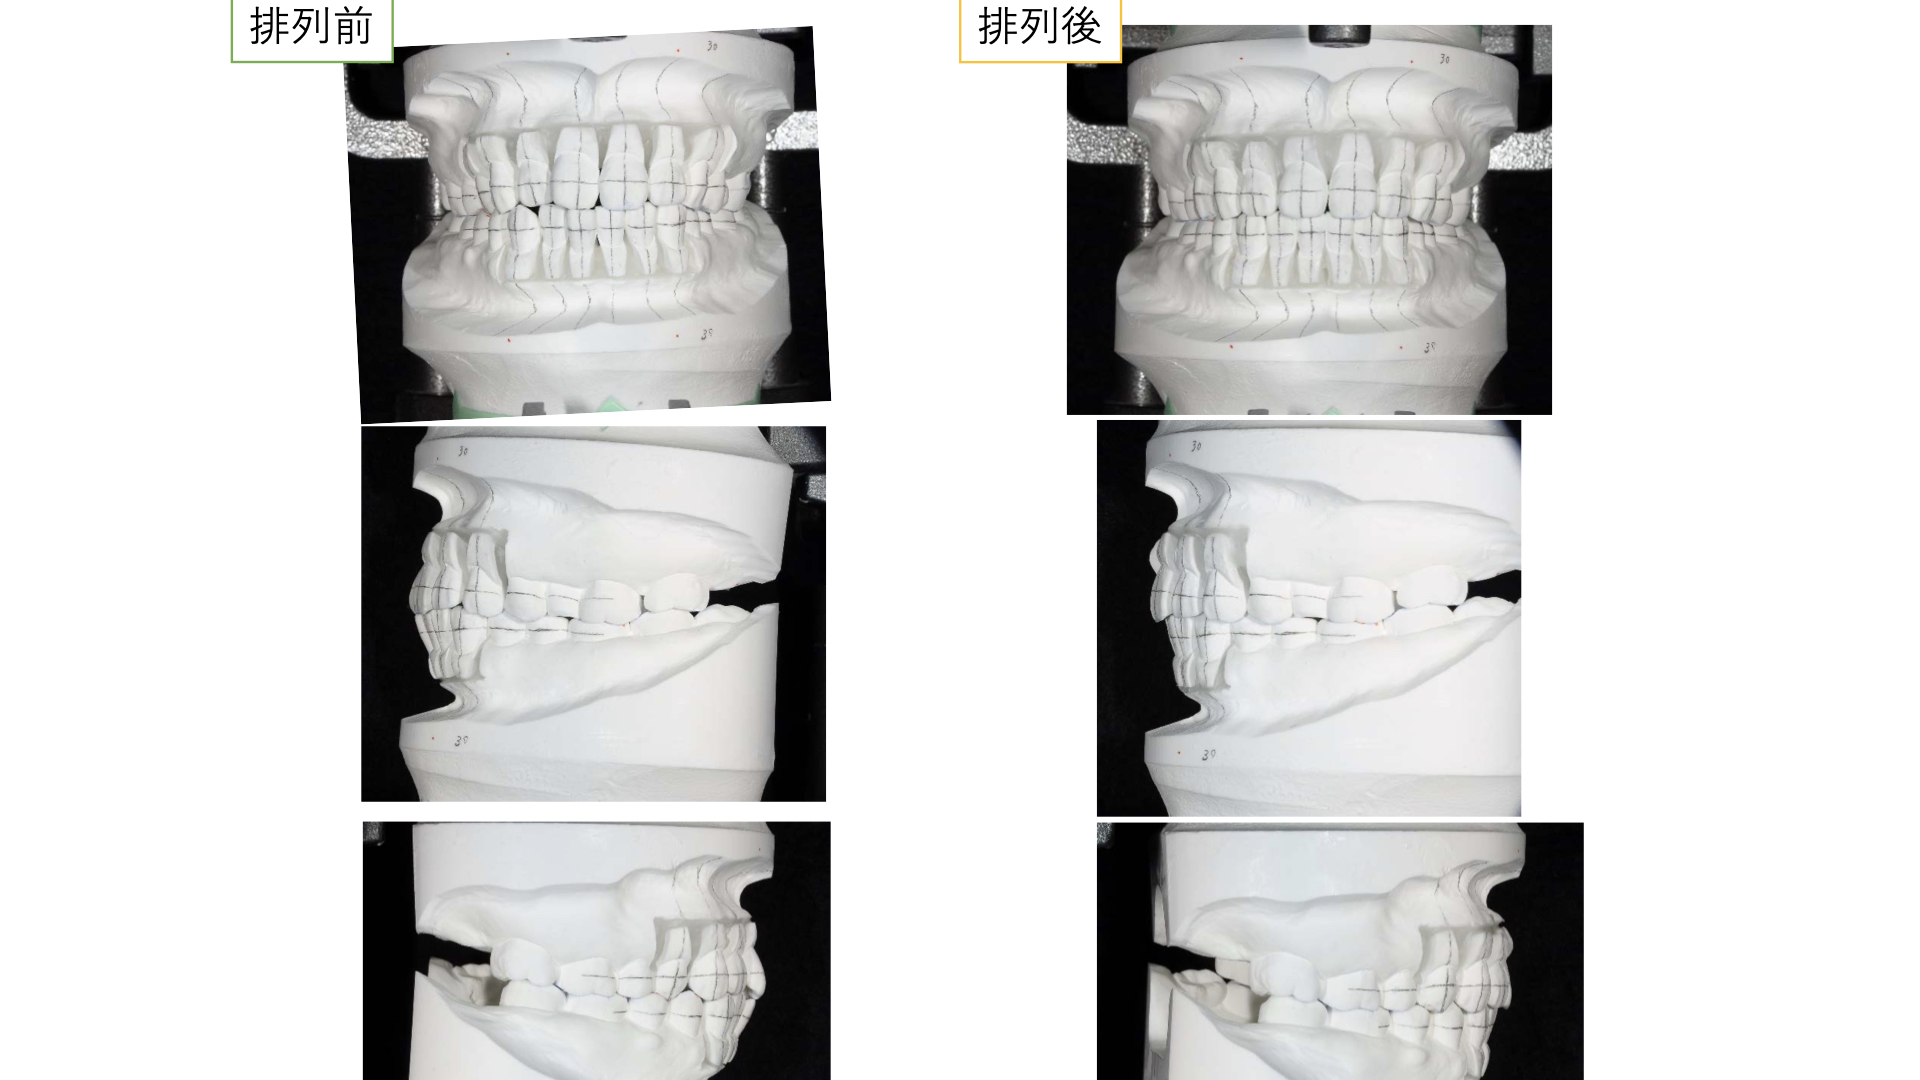

そこで矯正をせずに前歯を噛ませるにはどうしたらよいか。模型上でシミュレーションをしました。

すると、茶色のwaxの部分は足しているところで、鉛筆の斜線は削っているところです。

下の前歯はほとんど足す必要があり、多くの歯を治療しなければいけません。

どうしても全体的な矯正治療(平均2〜3年)を望まれなかったので、模型上で咬合調整をおこない、やや前歯が噛み合うところまで調整すると矯正治療期間が短くなります。

模型上で、そこから歯を並べて(排列)みて奥歯をさわらずに短い期間で矯正治療ができるのかをシミュレーションした結果

可能ということがわかったので、この計画にしました。